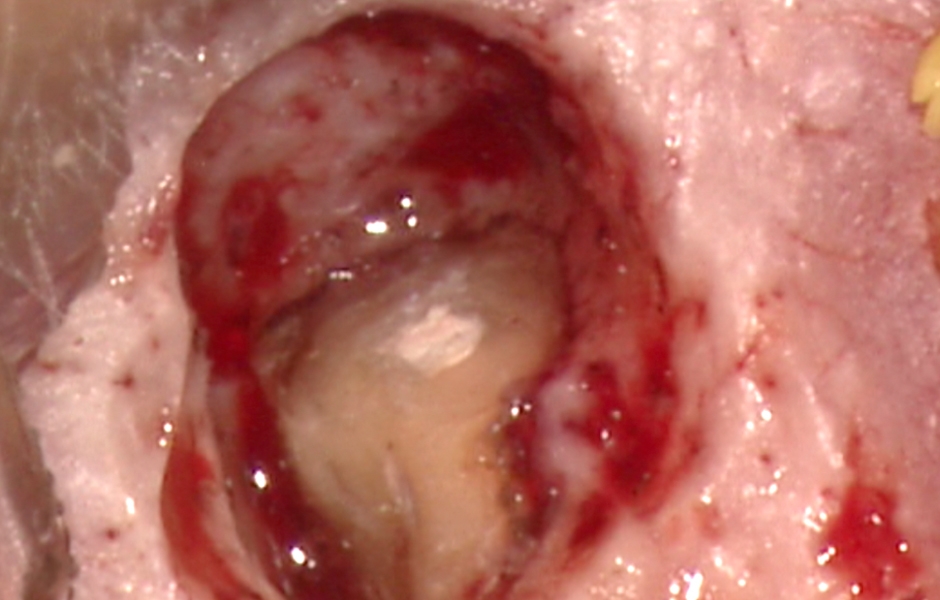

Obr. 1.3: Retrográdní výplň bílým MTA.

Obr. 2.6: Zavádění retrográdního výplňového materiálu do apikální preparace.

Obr. 2.7: Apikální i laterální preparace vyplněny bílým MTA.

Obr. 4.3: Retrográdní výplň MB1, MB2 a isthmu.